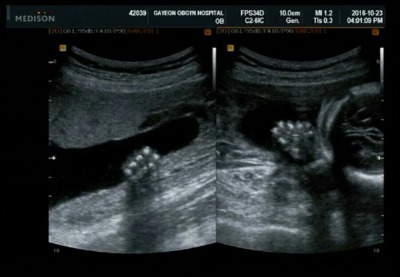

별똥22주)2차정밀초음파 성별확인!딸초음파♡

2016.10.23 2차정밀초음파 보던날! 한달만에 병원이라 설레기도 하고 성별반전은 없을지 걱정되기도 ..^^; ...